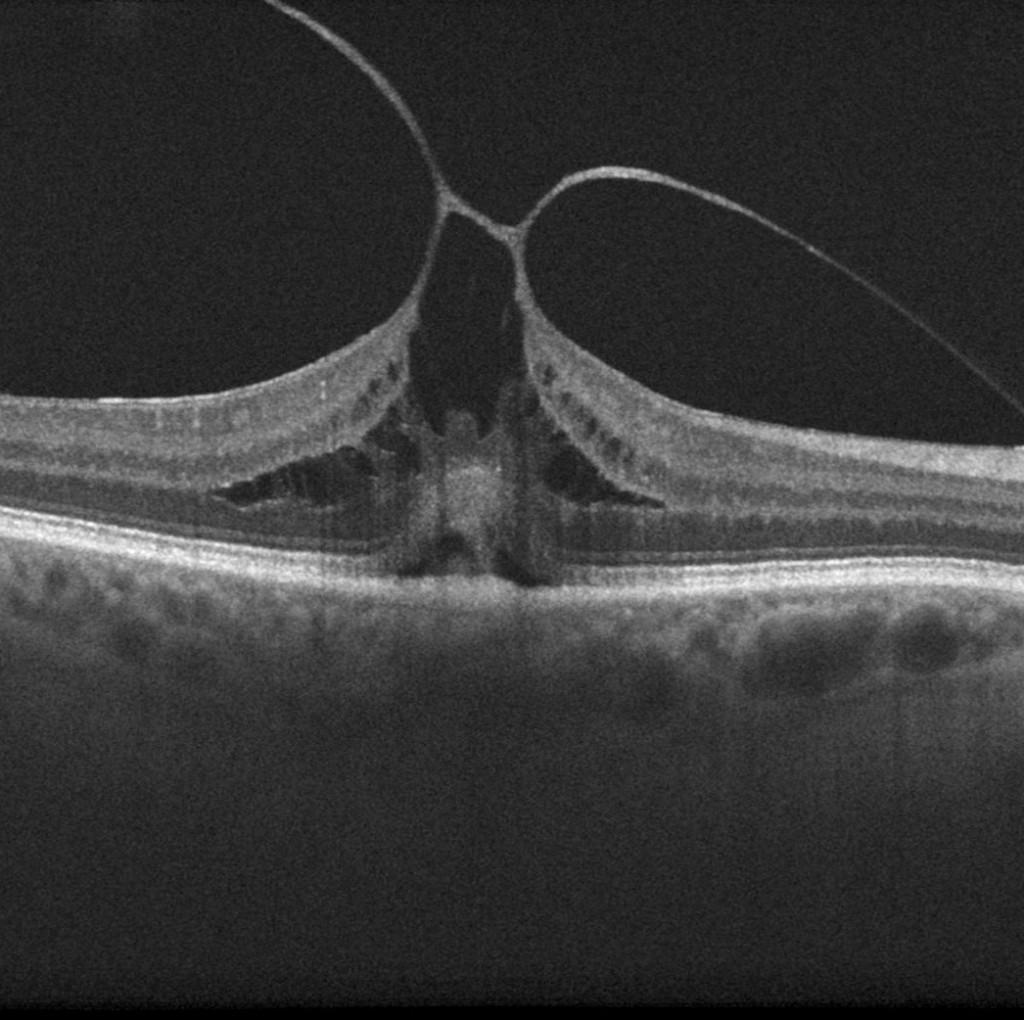

Published inVitrectomy for Vitreomacular Traction Syndrome